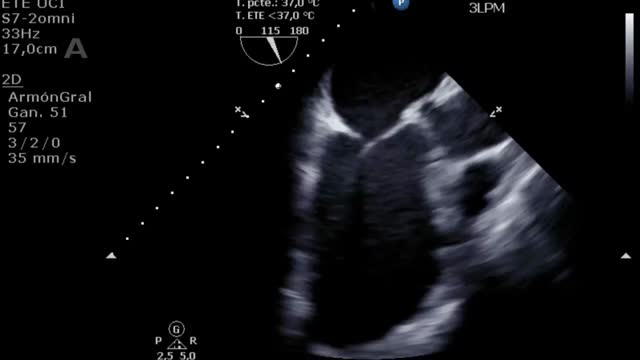

Por último, muchos de los pacientes con ECMO VA pueden tener algún otro dispositivo de asistencia ventricular izquierda (BCIAo, Impella®) como medida de descarga ventricular34 y de los que también deberemos controlar su posición y funcionamiento12. En el caso del BCIAo, mediante ETT/ETE podremos observar el inflado del balón a nivel de la aorta descendente con su extremo distal a nivel del nacimiento de la subclavia izquierda (suplementario 17). El Impella® se puede explorar tanto por ETT (paraesternal de eje largo o apical de 3 cámaras) como por ETE (mediesofágico 120°) y debemos observar el dispositivo entrando desde la aorta ascendente y el inlet o zona de succión a 3-4cm de la válvula aórtica35,36 (fig. 4 y suplementario 18).

El destete supone un proceso de descenso gradual (500ml cada 15-20min) del soporte de la ECMO VA de manera que se restablece progresivamente la precarga en el corazón. Para ello el paciente debe estar adecuadamente anticoagulado. Evaluaremos la repercusión hemodinámica (PVC, PAM y diferencial, SvO2, SatO2) y ecocardiográfica (FEVI, IVT, onda E, onda E’ o S’ del anillo mitral lateral) que tiene hasta un nivel (normalmente 1-1,5l/min) que nos indique que el paciente puede tolerar la retirada de la asistencia. Durante esta, evaluaremos que mantiene e incluso aumenta la FEVI por encima del 25-30%, la IVT por encima de 10cm y la onda S’ de más de 6cm/s (fig. 5 y suplementario 22). Junto con ello, también evaluaremos el comportamiento de las cavidades derechas (desplazamiento sistólico del plano del anillo tricuspídeo>16cm, S’>10cm/s y tamaño VD) y la posible aparición de signos de hipertensión pulmonar (aumento de la velocidad pico de la insuficiencia tricuspídea) que predigan un fracaso de VD38–40.

Evaluación ecocardiográfica de destete de paciente con ECMO VA. Ecografía transtorácica e integral velocidad-tiempo (IVT) del tracto de salida del ventrículo izquierdo al reducir flujo (A: 3L/min, B: 2,5L/min, C: 2L/min) de ECMO VA. Obsérvese el aumento del tamaño de la IVT y consecuentemente del volumen sistólico y del gasto cardiaco.